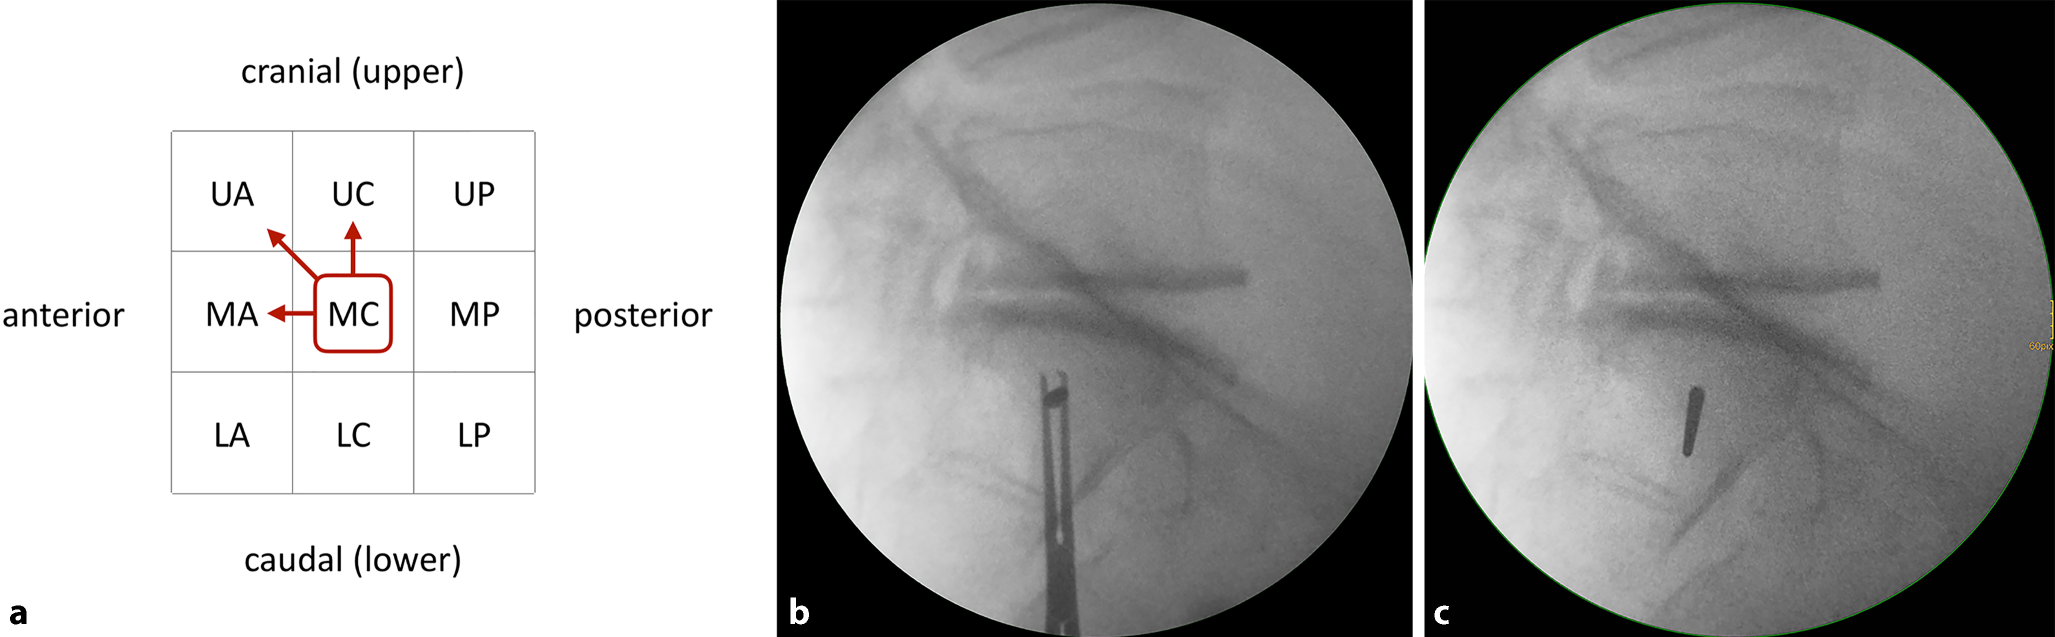

Intraoperatively, the S1 starting point is identified in the lateral view (Fig. 3a). For preoperative planning using multiplanar CT reconstructions, the lateral view at the level of the S1 body is segmented in a 3 × 3 grid with 9 zones. An upper, middle and lower third are distinguished from cranial to caudal, which corresponds to the outlet view. An anterior, central and posterior third are distinguished from anterior to posterior, which corresponds to the inlet view. Accordingly, the zones are labeled as acronyms of two uppercase letters. For example, the “UA” zone corresponds to the upper and anterior third, the “MC” zone to the middle and central third and the “LP” zone to the lower and posterior third.

Fig. 3

Third step of preoperative work-up: assessing transverse screw trajectories. a The lateral view at the level of the S1 body is segmented in a 3 × 3 grid with 9 zones, b transverse screw trajectory. U upper, M middle, L lower, A anterior, C central, P posterior, red circumscribed letters transverse screw trajectories with safe osseous corridors, Blue line coronal axis, green line sagittal axis

A transverse screw trajectory (Fig. 3b) following one of the nine zones is preferable over an oblique screw trajectory, which crosses zone borders, for the following two reasons. First, a transverse trajectory allows for the safe use of longer screws or even for the use of transiliac–transsacral screws or bars. Second, the intraoperative two-dimensional fluoroscopic control is much more demanding for oblique trajectories.

Within the transverse screw trajectories, central transverse trajectories (UC, MC and LC) are preferable over anterior and posterior transverse trajectories for the following reason. Small intraoperative deviations from preoperative planning may result in posterior screw misplacement for posterior transverse trajectories (UP, MP and LP) with consecutive iatrogenic lesions of sacral nerve roots in the sacral canal. Small intraoperative deviations from preoperative planning may result in anterior screw misplacement for anterior transverse trajectories (UA, MA and LA) with consecutive iatrogenic lesions of lumbar nerve roots. In contrast, central transverse trajectories may compensate for small intraoperative deviations.

The assessment of the MC transverse trajectory is the first choice due to its central location. This trajectory is therefore also called “Bullseye trajectory”. In the present case there is an adequate osseous corridor for an MC trajectory. There is also an UC trajectory, while the LC trajectory is in close vicinity to the S1 nerve roots. The transverse screw trajectories with safe osseous corridors (MC and UC) are marked in the grid as depicted. Even in the presence of safe transverse trajectories it is advisable to preoperatively also assess safe oblique trajectories as shown below in order to be able to intraoperatively judge whether small intraoperative deviations from the preoperative plan are acceptable.